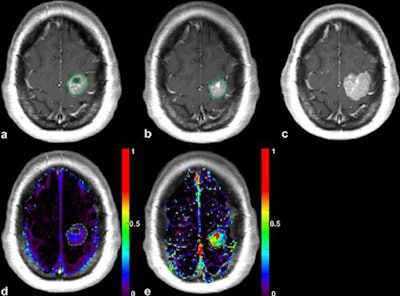

Lung cancer patients with brain metastases prospectively underwent conventional 3-tesla MRI at baseline, during treatment, and after treatment. DCE-MRI was performed at baseline and early post-treatment to evaluate certain pharmacokinetic parameters. The research team, led by Dr. Grégory Kuchcinski from the neuroradiology department at the University of Lille, in Lille, France, found the combination of DCE-MRI plus change in extravascular extracellular space per unit volume of tissue to be the best response predictor.

DCE-MRI enables the assessment of the blood-brain barrier (BBB) integrity and neoangiogenesis within brain tumors by tracking changes in a gadolinium contrast agent. The researchers hypothesized that increased BBB permeability and neoangiogenesis in brain metastases were associated with a better response to antineoplastic therapy and the early variation of the DCE-MRI parameters could be predictive of the objective response.

An additional DCE-MRI sequence was performed during baseline and early post-treatment MRI to evaluate baseline pharmacokinetic parameters and their early variation. The objective response was evaluated by the volume variation of each metastasis from baseline to midterm MRI. Receiver operating characteristic curve analysis determined the best DCE-MRI parameter to predict the objective response.